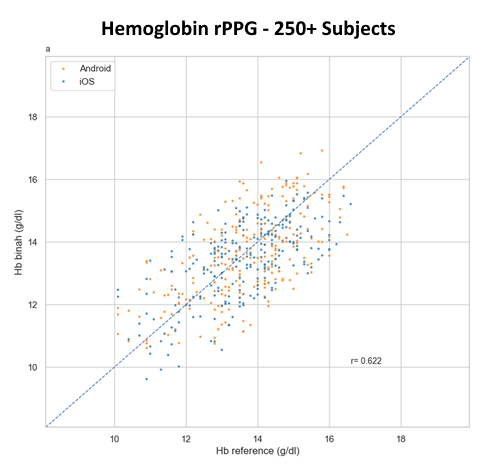

Briah.ai’s technology can measure blood pressure, heart rate, heart rate variability, respiration rate, hemoglobin, and hemoglobin A1C.

How accurate are the measurements provided by Briah.ai?

Our technology meets high accuracy standards and has been validated through extensive research and testing.